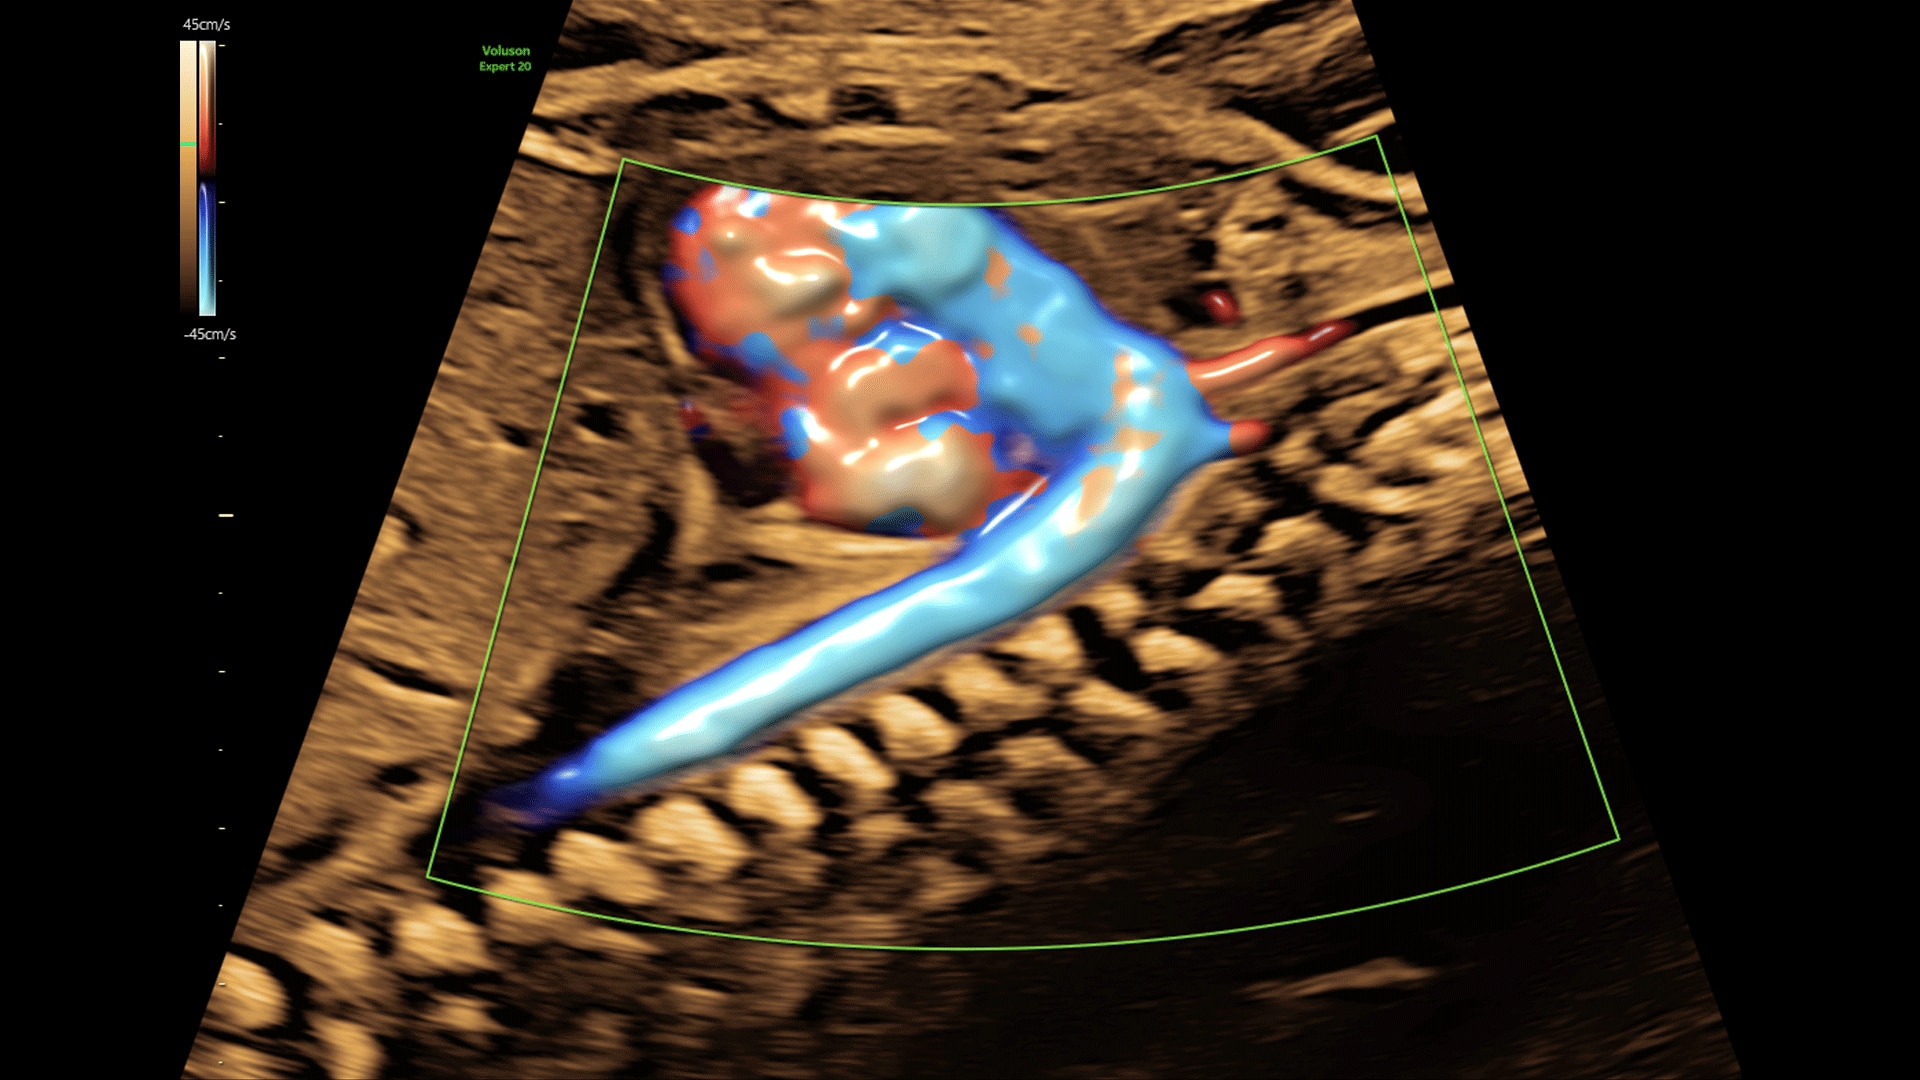

Amplify imaging performance and simplify scanning with our most advanced architecture

Extraordinary clarity and definition so you can focus on early detection and intervention.

Faster.Sharper. Clearer.

Faster.Sharper. Clearer.